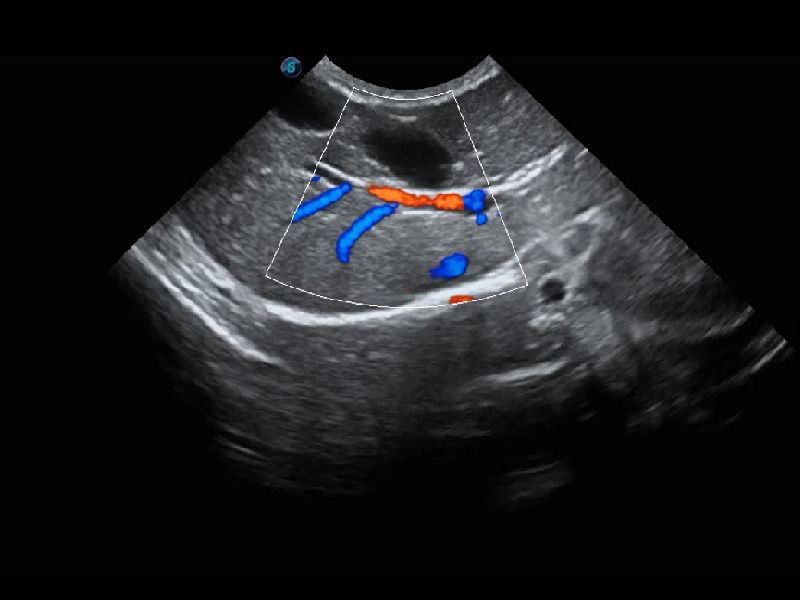

4T血流成像 微察秋毫

融合不同血流成像技术的优势,即可以提升血流成束性,同时可提高血流的视觉敏感性。

PDI 能量多普勒血流

提供高灵敏度和空间分辦率的血流图像,获得更加真实和丰富的诊断信息。

SR Flow 高分辨率血流成像

能够清晰显示细小、低速血流图像,获取传统彩色多普勒技术难以得到的细节和信息。

(犬)肾脏血流